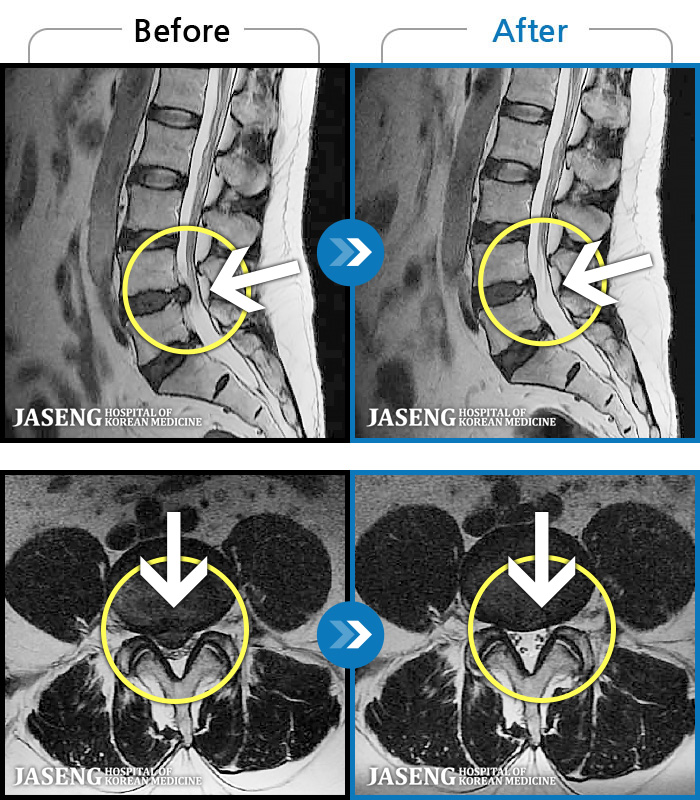

[ؿ] 24.10.10~25.04.23